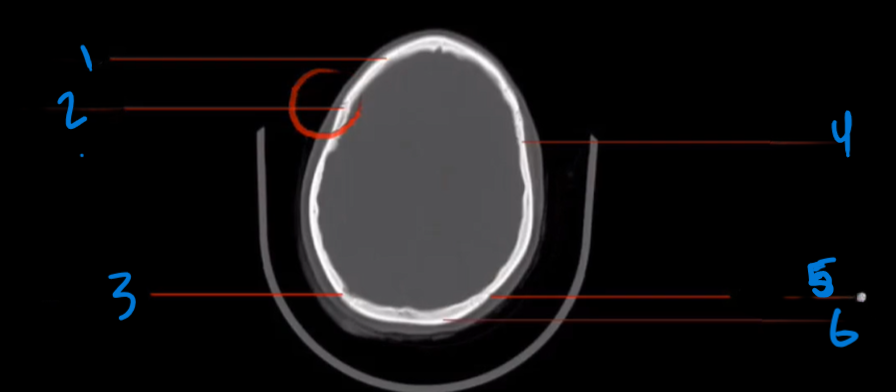

What is the landmark of # 1 called?

Frontal Bone

What is the landmark # 2 called?

Frontal Sinus

What is landmark # 3 called?

Orbital roof